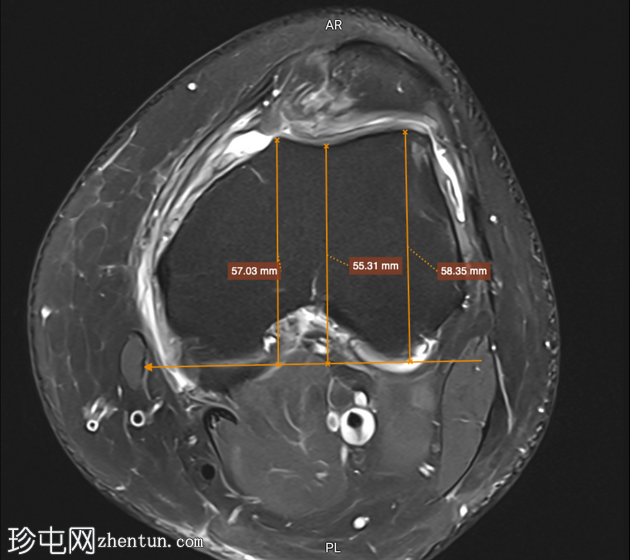

轴位PD序列

脂肪抑制序列

标注图像

5.png

滑车

深度

滑车沟

6.png

角度

滑车外侧

7.png

倾斜度

8.png

改良的

Insall-Salvati 比值

滑车深度 < 3 mm

滑车沟角度 > 150°

滑车外侧倾斜度 < 11°

影像学表现符合滑车发育不良

改良的 Insall-Salvati 比值 1.7(在正常范围内)